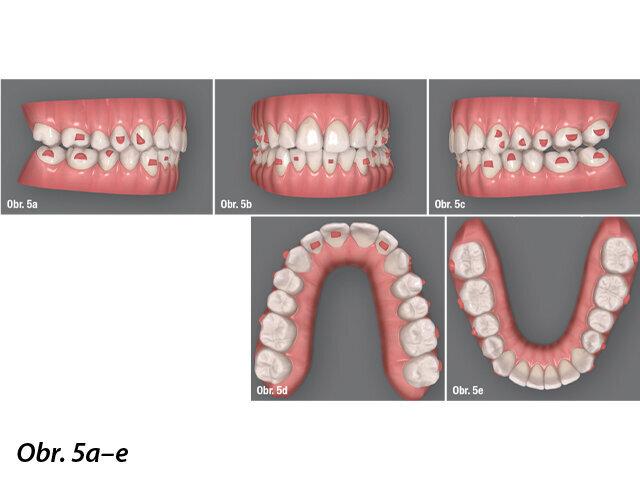

Po dokončení první části plánované léčby s alignery byla úspěšnost ortodontických pohybů naprogramovaných pomocí softwaru vyšší než 95 % (obr. 5). Oblouky získaly anatomický tvar a zkřížený skus a vztah II. třídy na levé straně byly opraveny. Došlo také ke zmírnění stěsnání zubů v obou čelistech a ke srovnání středové čáry. Průběžný klinický nález zahrnoval postranní otevřený skus jako výsledek pasivní laterální intruze v důsledku tloušťky materiálu alignerů a předčasných kontaktů na předních zubech. V oblasti dolních řezáků byly potřebné drobné doplňující posuny. K vyřešení těchto problémů tedy byla naplánována druhá fáze léčby pomocí alignerů, aby se zuby dostaly do finální pozice. Druhý plán léčby ClinCheck počítal s 16 alignery na horní a dolní čelist pro posteriorní extruzi a retrakci dolních řezáků, aby se uvolnil kontakt a bylo možné uzavřít laterálně otevřený skus. Pacientka pokračovala v používání vibračního přístroje a interval pro výměnu alignerů byl stanoven na pět dnů a následně byl zkrácen na tři dny. Poslední alignery pacientka nosila pouze dvanáct hodin denně, aby došlo k pasivnímu uzavření laterálního otevřeného skusu.